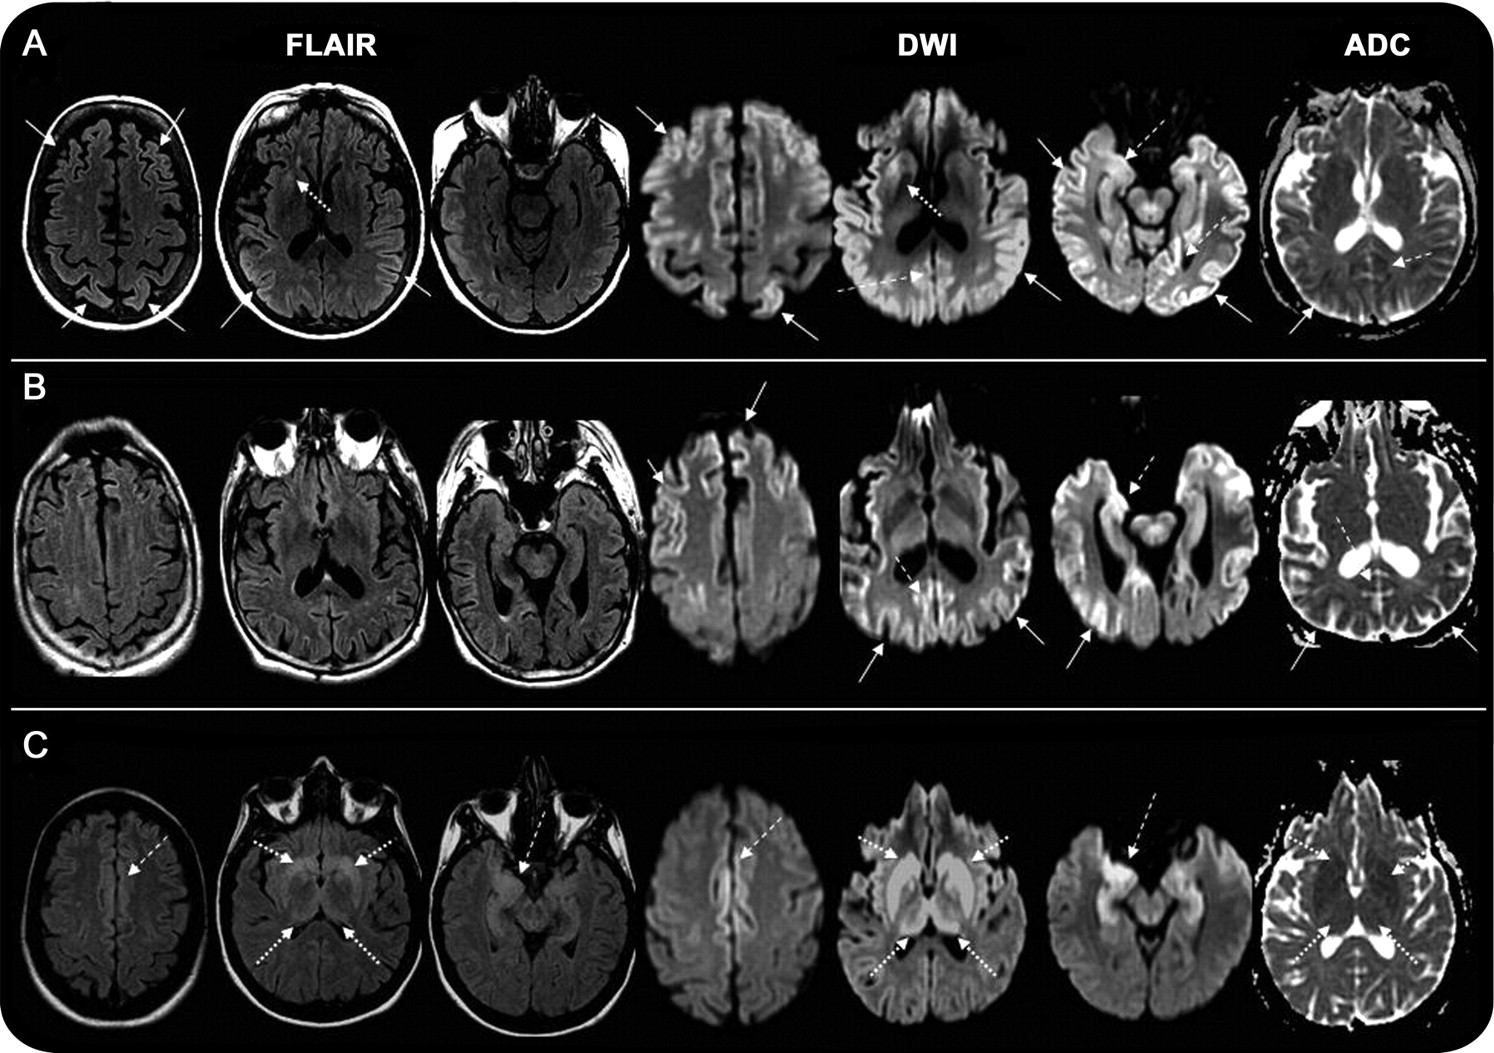

(一)fCJD病例(E200K突变)显示皮层(实心箭头)参与右脑更加明显,尤其是在右额叶,边缘参与(虚线箭头)更加明显正确的前扣带和正确的脑岛皮层下(虚线箭头)hyperintensities diffusion-weighted成像(驾车)大于fluid-attenuated反转恢复(天赋)图像。注意,皮层下表观扩散系数(ADC) hypointensity双边纹状体。这张照片是读克雅氏病(CJD)。(B) GSS案例(F198S突变)双边边缘hyperintensity前扣带,脑岛,和微妙的mesiotemporal皮层的参与,同样明显醉酒驾车和天赋的图像。图像读取库贾氏症。(C)一个边缘脑病npRPD情况由于anti-AMPAR anti-Sox2抗体和小细胞肺癌。注意重要的双边hyperintensity mesiotemporal皮层(包括海马和杏仁核),脑岛,和扣带,在天赋比醉酒驾车的图像。图像读取库贾氏症。

核磁共振特性遗传朊病毒疾病。

模式和频率酒后驾车和天赋hyperintensities家族库贾氏症患者之间的不同(fCJD)和患者Gerstmann-Straussler-Scheinker (GSS) (图1和3)。五6 fCJD核磁共振成像的灰质hyperintensities和阅读是积极的;4 (3 E200K和1 D178N密码子129 vv)弥漫性(边缘皮层,皮层下)的参与,和1 (V180I)只有皮层hyperintensities。第六届主题与fCJD没有hyperintensities (5-octapeptide重复)。7 GSS核磁共振成像,只有一个是阅读积极(F198S),与皮层过程(边缘,大脑皮层和纹状体)醉酒驾车。两个(A117V和另一个F198S)只有边缘hyperintensities,天赋和醉酒驾车。剩下的4 (P102L和3 A117V)没有灰质异常。

我们患者的磁共振成像模式fCJD通常与sCJD,但在大多数GSS情况下,这种模式不存在。皮层下ADC地图只有在检查与醉酒驾车皮层下hyperintensity病例,研究后,我们注意到皮层下ADC hypointensity不醉酒驾车hyperintensity在某些GSS情况;这可能是由于“T2停电”效应。尽管P102L案件没有典型sCJD MRI发现,和随后的情况下也没有见过在我们的中心,至少有一个案例被报道有一个经典的库贾氏症MRI。38